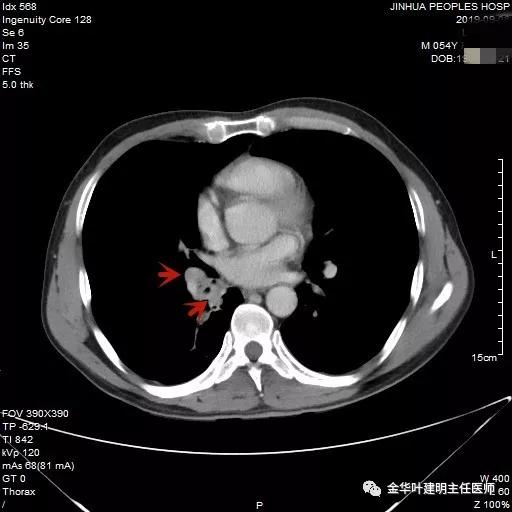

上图示肿瘤堵塞管腔

上面各图示肿瘤位于肺门部,堵塞下叶及中间支气管

我们仔细看了增强CT,纵隔未见确切疑似转移的肿大淋巴结,这样的情况下,是不是再次气管镜活检,还是直接可以手术?当然从原则上来讲,应该再重新纤支镜检查,再活检以取得病理确诊后,再行手术。但个人以为,从影像及气管镜所见来讲,临床诊断已经可以确定为肺癌,而且中央型的以鳞癌为多见,当然也有的会是小细胞癌,不过小细胞癌一般很早就会有纵隔淋巴结转移,如果患者及家属理解,我认为从减少痛苦、节约经费、节省时间等方面考虑,直接手术也基本不会错的。当然所有的利弊与可能都要如实与患者及家属沟通,并征求他们的意见,最终李某及家属选择不再重新纤支镜检查与活检,要求直接手术。

手术怎么做?中下叶切除肯定不行,肿瘤距中间支气管开口才3毫米,切缘一定会阳性的。那么是不是要全肺切除呢?虽然李某才56岁,右全肺可能也吃的消,但合并存在冠心病,又是右全肺不是左全肺切除,况且右上叶开口没有累及,显然直接切除右全肺是不妥的,也是可惜的。那么最适合的就是行“右肺中下叶袖式切除术”!也就是说把右中下叶的共干(中间支气管)连同其开口于右主支气管处都切除,同时也就切断了右上叶开口处,然后将右上叶支气管与右主支气管吻合起来。袖式肺叶切除在肺切除术中算是难度与风险都大的手术,当然如果肺动脉也要袖切,即所谓的双袖切则更是高难度手术。但在基层医院来讲,单支气管袖式肺叶切除也不是常见的手术,而是已经可以算高难度术式了。在袖式肺叶切除中,因为解剖关系与角度、支气管口径匹配等原因,右上叶袖式切除相对容易一点,也最为常见(点击链接:1小时40分钟:胸腔镜辅助下右肺上叶袖形切除)。我们诊疗组也有不少相关经验,但对于中下叶的袖式肺叶切除则更少见些,我们还是第一次,而且上叶支气管的口径与右主支气管相差较大,吻合时如何匹配需要术者更高的技术水平与缝合功底。